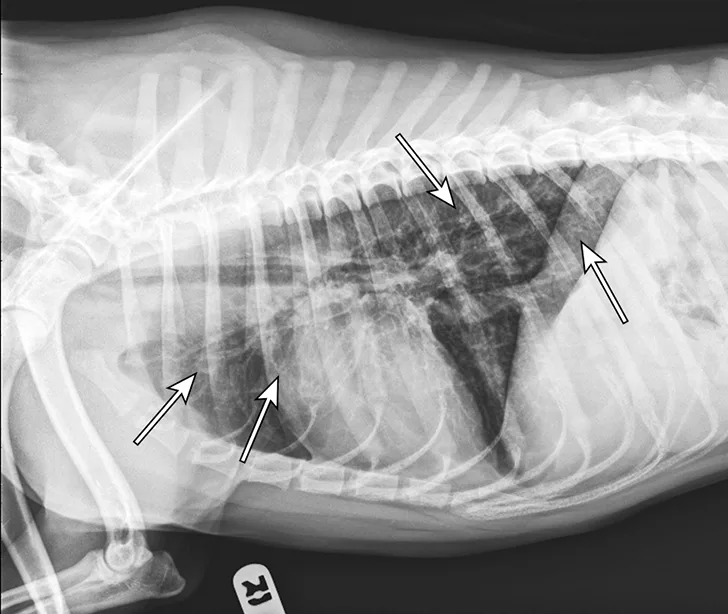

At 1 month after discharge, thoracic radiography was repeated and revealed marked improvement in diffusion of the bronchointerstitial pattern (Figure 4). Prednisone was tapered over the next 6 weeks to 10 mg every other day. Intermittent coughing returned, and the dosage was increased to 10 mg once daily (0.33 mg/kg/day), which maintained clinical control. Because this regimen did not result in significant adverse effects and maintained clinical control, adjunctive or alternative anti-inflammatory medications were not prescribed.

Radiograph 1 month after therapeutic initiation showing an improved bronchointerstitial pattern

Thoracic radiographs showing a characteristic diffuse, patchy bronchointerstitial pattern (arrows)